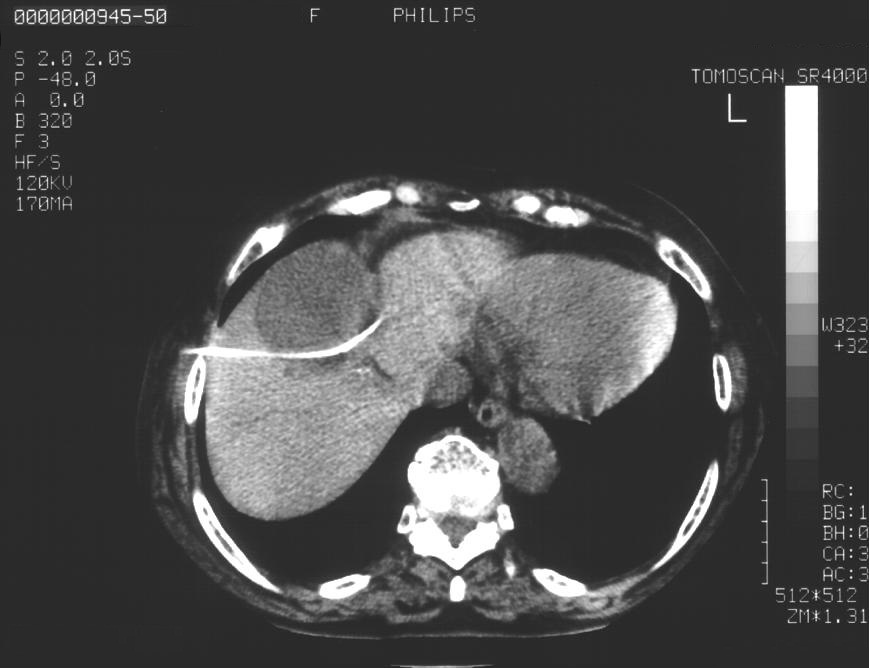

19.7.1. Percutaneous ethanol cyst sclerotization (liver, spleen, kidney)

During US and CT examinations simplex cystic lesions are often accidentally encountered that do not cause any pain for the patient. Cysts of the liver, spleen or the kidneys cause discomfort or pain for the patients need to be therapeutically addressed.

Compared to the surgical methods of past, nowadays these cystic lesions can be successfully treated percutaneously with alcoholic cyst sclerotization. (Figures 26., 27.).

Image

Figure 26. – Percutaneous ethanol cyst sclerotization ( filling up of the cyst before the sclerotization)

A

B

Figure 27. – US and CT examinations before percutaneous ethanol sclerotization (A: US examination, B: CT examination)

The puncture of the cyst is usually guided with US (rarely with CT). The puncturing needs to take place from the parenchymal side of the cyst. When its contents are removed the empty cavity is filled up with diluted contrast material to ensure that there is no contrast leakage to the surroundings. The 96% ethanol is only injected after the contrast material has been removed and no leakage was found. (The volume of the alcohol should not exceed 50-60% of the cyst or 100 ml.)

The injected ethanol is left in the cyst for 20 minutes. Following this, the alcohol is drained as well. Cystic regression is then regularly controlled with US or CT examinations. (Figures 28., 29.) Patient complaints usually cease within 4-6 weeks after the treatment.